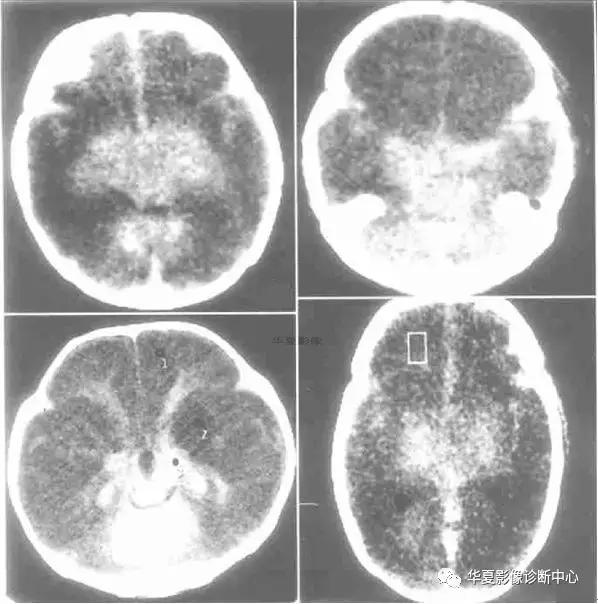

儿童弥漫性脑白质和灰质的密度减低、伴有灰白质界限不清或消失,或灰白质密度反转,而丘脑、脑干和小脑密度相对增高根据“反转征”出现时间分急性和慢性2期。急性指当时CT扫描即有“反转征”,慢性为弥漫性脑萎缩/脑软化伴“反转征”。急性期神经病理学改变主要为大脑皮质和白质发生急性神经元坏死和脑水肿,脑干及丘脑淤点状出血。Baenziter等认为缺氧缺血后大脑皮层第Ⅲ、Ⅳ层神经细胞最易受损,缺血后12小时以上大脑皮层神经细胞即发生嗜酸样变性,基质发生凝固性坏死,2~3 天轴索开始变性,7天左右出现成胶质细胞、脂肪颗粒和新生血管,2~4周形成空洞和软化,进一步论述了缺氧缺血后皮层神经细胞的病理过程。基底节和丘脑损害所发生的密度增高目前有几种认识:国内学者认为系缺氧后上述区域发生大理石样变性所致,表现为神经元的丧失、星形细胞胶样变性及髓鞘过度形成,尤其壳核背外侧与丘脑腹外侧髓鞘化最活跃,需氧量最高,代谢旺盛,对缺氧缺血敏感,因此受累也最为严重。有的则认为是严重缺血后1~2周新生毛细血管网的大量增加或与大脑的白质深部髓质静脉扩张淤血有关,甚至有人认为不是密度增高,而是正常脑策划密度。这种密度增高是相对的,虽然在急性期脑中央区域的密度增高个体间存在一定的密度差异,但本组从未见有像脑血管破裂出血那样的高密度,CT值多在22 HU左右,因此这种密度增高是相对的。

“反转征”的分期,急性期应以生后当时CT扫描结果为准。一般来说,生后3天多以脑水肿为主,其后为脑实质缺氧缺血性损害,所以生后5~10 天扫描较为可靠。慢性期以生后3~8周为妥,此期已出现明显脑软化、脑萎缩,脑实质密度明显低于急性期。急性“反转征”的患儿需要呼吸支持和重症监护,延误治疗者可转变为慢性“反转征”,其密度变化更具有特征性。有人认为重症病人在3个月时即可发生脑软化和脑萎缩,发生率约占HIE病例的20%。与此同时,丘脑与脑干的密度增高较急性期更加显著,如同“增强”一样,CT值22~26 HU,丘脑形态轮廓勾画清楚,犹如雪山的“山丘”,出现这种明显反差的影像学表现可能与脑软化的低密度衬托有关,若不仔细的观察和测量CT值易误为脑出血。

“反转征”主要发生在重度HIE病例中,因此“反转征”可视为重度HIE少见而重要的征象,可把它作为HIE诊断及分级和评价预后的重要依据。

CT“反转征”是新生儿重度缺氧缺血性脑损伤的一种重要CT征象,但并非特异性,也可以在某些疾病中如外伤(虐待伤)、病毒性脑炎等出现。特别应注意慢性“反转征”与HIE的并发症鉴别。众所周知,HIE常见并发症为外部性脑积水和局限性脑软化灶和脑萎缩,前者不存在鉴别问题,后者CT上脑软化灶多发生在顶枕叶或双侧脑室旁白质内,多为局限性,而慢性“反转征”则表现为半球弥漫性低密度区,同时基底节及丘脑等脑中央区域密度增高明显,表现特殊,这点对鉴别诊断有相当重要的价值。因此,重度窒息儿大脑灰白质密度弥漫性减低伴灰白质界限消失或密度反转以及基底节、丘脑、脑干和小脑密度相对增高是重度HIE的特征性CT表现,是诊断急、慢性CT“反转征”的重要依据。急性期脑室受压变窄和慢性期脑室扩大主要与脑水肿和脑软化/脑萎缩有关。“反转征”一旦出现,高度提示脑策划有不可逆性脑损伤存在,预后大多不良,即使存活也将发生脑瘫或智力障碍等后遗症。